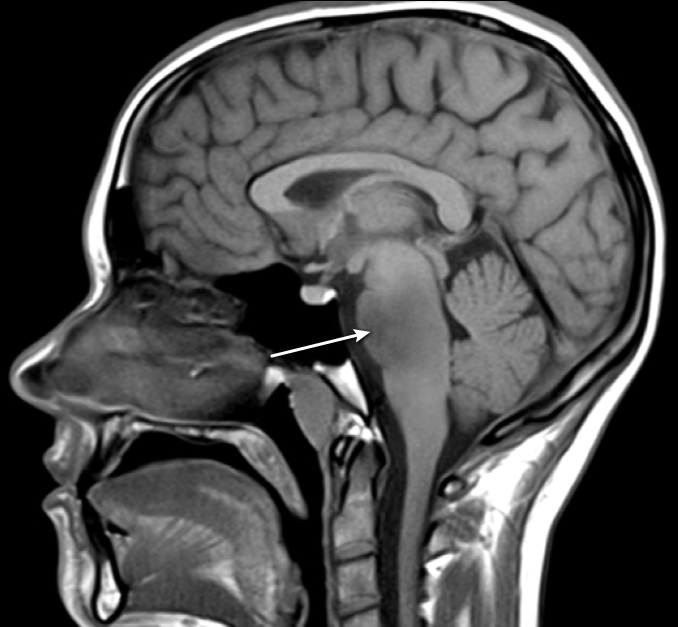

A 12-year-old child is being assessed for severe headaches that have been bothering him for several months. He has also experienced paresthesia, weakness, and extremity rigidity. As illustrated in the figure below, an MRI of the brain reveals an expansile mass in the lower pons: A 12-year-old child is being assessed for severe headaches that have been bothering him for several months. He has also experienced paresthesia, weakness, and extremity rigidity. As illustrated in the figure below, an MRI of the brain reveals an expansile mass in the lower pons:   Which of the following is most likely to be noticed in this patient as a result of the brain lesion's direct involvement of nerve nuclei? A) Asymmetric pupils B) Spontaneous nystagmus C) Tongue atrophy D) Trapezius weakness E) Vertical diplopia Which of the following is most likely to be noticed in this patient as a result of the brain lesion's direct involvement of nerve nuclei?